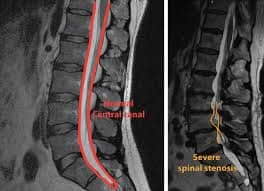

Magnetic Resonance Imaging

Magnetic Resonance Imaging (MRI) is a crucial medical imaging technique used for the diagnosis and evaluation of various medical conditions. The Department of Radiology and Imaging Sciences appears to be well-equipped with state-of-the-art MRI technology, which plays a pivotal role in accurate diagnosis and treatment planning. Here's a breakdown of the services and advanced applications offered by the department:

Our Highfields 3T system is essential for performing advanced applications such as diffuse and perfusion imaging for stroke assessment, tractography, and volumetric spectroscopy. These cutting-edge techniques can only be conducted using our specialized 3T system.